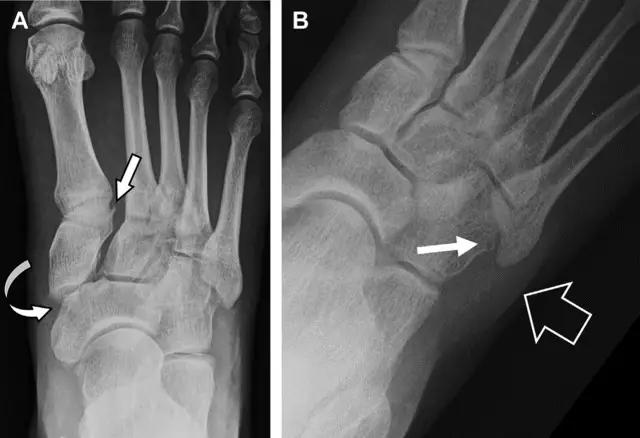

22 跗跖关节复合体(Lisfranc 关节复合体)损伤

与跗跖关节韧带相关的骨折常由旋前或旋后的跖屈损伤引起。尽管跗跖关节骨折脱位仅占所有骨折的 0.2%,但是约 20% 的这些骨折在初次检查时被漏诊。初次 X 片可能示正常,但是负重位 X 线片常常提示脱位或半脱位。典型表现:第二跖骨底和内侧楔骨之间的骨折碎片,跖骨间间隙增宽(图 8)。脱位亦可发生在舟骨-内侧楔骨关节,导致另一种变异的跗跖关节损伤(图 9A)。此外,骰骨的小块皮质撕脱在足部斜位片上可清晰显示(图 9B)。

图 8 从马上摔落的患者,跗跖关节骨折。A 正位片示内侧楔骨旁边的小骨折碎片(箭头),第二跖骨底向外半脱位;B 负重位侧位片示第二跖骨相对中间楔骨向背侧轻微移位(长方形);C STIR 序列 MRI 图像示跗跖关节韧带断裂(箭头),第一至第三跖骨、内侧楔骨及中间楔骨均骨髓水肿

图 9 变异的跗跖关节骨折。A 另一种类型的跗跖关节损伤,中间楔骨向内侧半脱位(弧形箭头),从而使第一、第二跖骨间间隙变宽,需注意,骨折在靠近内侧楔骨处(箭头);B 外侧跗跖关节损伤伴随从骰骨跖骨韧带的骰骨撕脱(箭头),需注意,第五跖骨底近端处存在软组织水肿(空箭头)